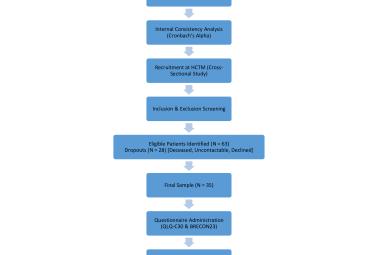

One of the notable complications of impacted mandibular third molar (MTM) is distal caries of the mandibular second molar (MSM) which can eventually lead to its early loss. The present study aimed to investigate the incidence of dental caries in MSM associated with impacted MTM and to propose an assessment protocol for MTM management. Patients’ dental records with dental panoramic tomography (DPT) imaging were studied retrospectively, in total 583 MTM images were evaluated. The presence of MSM distal caries, patient’s details, impaction depth, pattern and angulation of MTM and the distances between distal MSM and mesial MTM were assessed. Logistic regression analysis was performed on the data set. The highest caries incidence was observed in mesioangular impacted MTM (34.1%). Majority of the caries found were Level A (27.9%) and Class II (27.0%). The highest distance between distal MSM and MTM contributing to caries was 0.70-0.99 cm (31.9%). Patients’ age, angulation, pattern and depth of impacted MTM are the predictors which significantly increase the caries incidence in MSM (p<0.05). Prophylactic removal of MTM should be proposed when the distance of mesial impacted MTM and distal MSM is around 0.70-0.99 cm, and is mesially angulated with IIA classification.